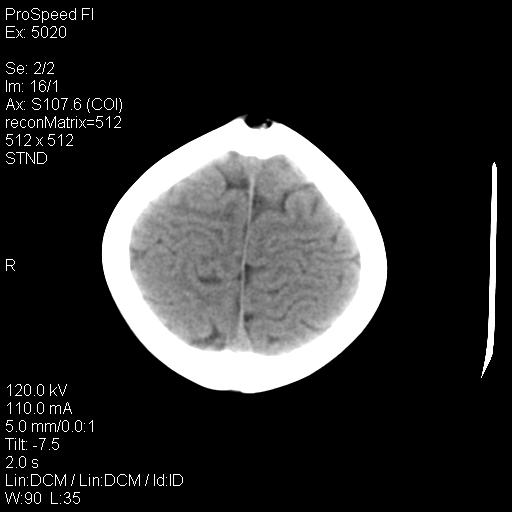

标题: PED1637:M 6Y 顶部无痛性包块两月。 [打印本页]

标题: PED1637:M 6Y 顶部无痛性包块两月。

2、颅骨局部缺失,边缘光滑、整齐

颅骨的病损表现为内外颅骨板层不规则的锋利的破坏,形成“斜边缘”,有一定的特点

颅骨为好发部位,生长缓慢,常位于顶骨、枕骨及颞骨,表现为颅骨缺损,呈圆形或椭圆形,边界清,无硬化

事发冠状缝与矢状缝交界区,密度较低,考虑表皮样囊肿可能性大,其次不除外嗜酸性肉芽肿